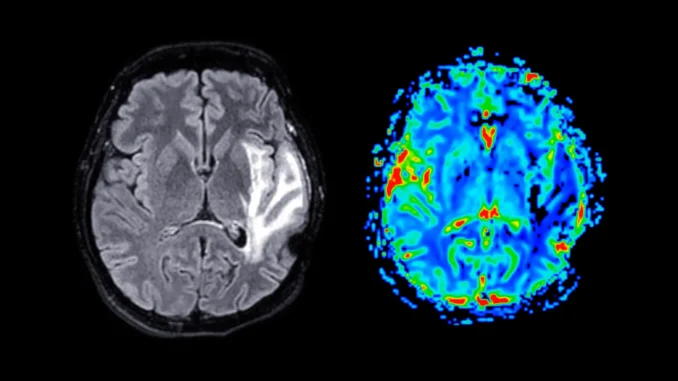

Dementia is a growing global public health problem and there is currently no cure. People affected by this condition experience a severe decline in mental abilities, including memory, thinking and reasoning, which can significantly interfere with daily life.

Dementia refers to a group of brain disorders rather than a single disease. The most common forms are Alzheimer’s disease, vascular dementia and mixed dementia. These conditions gradually damage nerve cells in the brain, and symptoms worsen over time. As the disease progresses, people may struggle with memory, language, problem solving and behavioral changes.